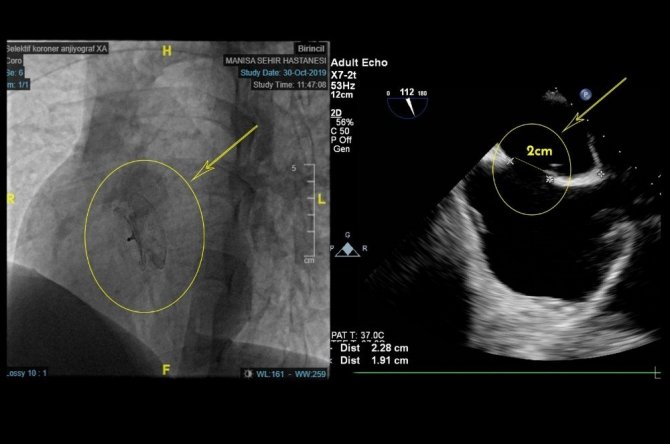

Yaklaşık bir yıldır süren nefes darlığı şikayetleri ile Manisa Şehir Hastanesine müracaat eden hasta Tolga Köz’ün EKO Kardiyografide 2 santimetre genişliğinde ASD (Atriyal Septal Defekt / Kalp Deliği) saptandı. Manisa Şehir Hastanesi Kardiyoloji Kliniğinde gerçekleştirilen işlemin ardından hasta sağlıklı bir şekilde taburcu edildi.

Kalp deliği hakkında bilgiler veren Uzm. Dr. Habil Yücel, "Doğuştan kalbin delik olması yani ASD (Atrial Septal Defekt), kalp kulakçıkları arasındaki duvarda açıklık bulunması durumudur. Bu yüzden akciğerlerde oksijenlenmiş kanın bir kısmı kısa devre yaparak sağ kalbe geçiyor. Bu olay yıllar içinde akciğere giden kanın artmasına, akciğer damarlarında basınç yükselmesine, kalp kasında hasara, nefes darlığına, ritim bozukluklarına ve kalp yetmezliğine neden olabiliyor. Hastalık, çocuklukta belirti verebildiği gibi uzun yıllar hiçbir şikayete neden olmadan da varlığını sürdürebiliyor. Hastamız Tolga’nın da kalbindeki delik yapılan tetkiklerden sonra şemsiyeye benzer birkaç milimlik bir cihazın anjiyoyla yerleştirilmesi sayesinde kapatıldı ve bir gün sonra sağlıkla taburcu ettik.” dedi.